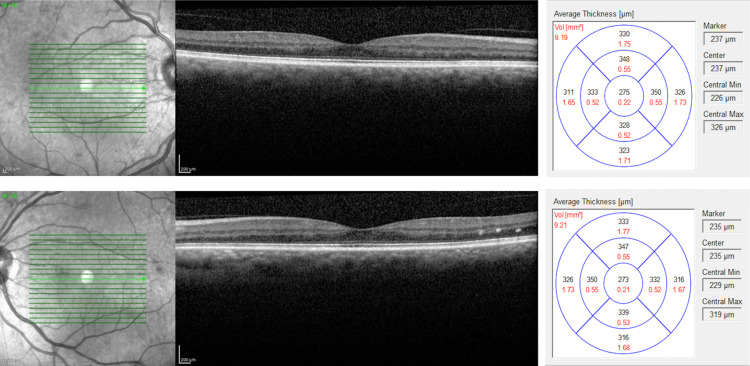

On examination, her visual acuity (VA) with her habitual glasses was 20/60 in the right eye (OD) and 20/70 in the left eye (OS), pin holed to 20/40 OD and 20/40 OS. The pupils were round and reactive to light OU, with no relative afferent pupillary defect. External examination, extraocular muscle movements, and counting finger visual field tests were normal. Her intraocular pressure was 16 mmHg in the right eye and 17 mmHg in the left eye, measured with a tonopen. The dilated fundus examination revealed rare cotton wool spots, microaneurysm, dot-blot hemorrhages, and vascular attenuation consistent with moderate, non-proliferative diabetic retinopathy in both eyes without any signs of macular edema (Figure 1). Her optic cups appeared normal with no signs of glaucoma. Given her decrease in vision and clinical presentation of non-proliferative diabetic maculopathy, we decided to run a macular optical coherence tomography (OCT) scan (Figure 2). The fovea showed a normal contour, no central macular edema, and an average central retinal thickness of 275 µM OD and 273 µM OS.